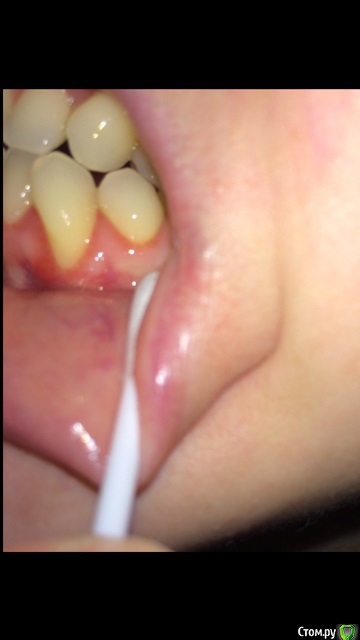

lalafa Опубликовано 16 августа, 2017 Поделиться Опубликовано 16 августа, 2017 (изменено) Здравствуйте, помогите, пожалуйста, советами.Мне 29 лет. Хронические заболевания - гранулезный фарингит, гастрит, ГЭРБ, сколиоз. У меня генерализованная рецессия десны, катаральный гингивит, пародонтальных карманов нет. Рекомендовано ортодонтическое лечение. НО ортодонты предупредили, что велика вероятность продолжения рецессии десны во время лечения и ухудшения ситуации. Посетила 2 пародонтологов, мнения противоположные. Один рекомендует операцию по закрытию рецессии методом пересадки трансплантата с неба. Хочет оперировать до ортодонт лечения самые проблемные зубы - клыки на нижней челюсти и 4ку. Мотив - утолщить десну, чтобы она выдержала брекеты и не рецессировала еще больше.Другой пародонтолог говорит, что так как именно эти зубы "не стоят в зубной дуге" (цитата врача) трансплантат с неба не приживется и результата не будет. Советует делать операцию после снятия брекетов на прямые зубы.Вопросы:1) Насколько в принципе опасно при такой рецессии проводить ортодонтическое лечение? зубы могут расшатываться и выпасть в процессе лечения?2) Закрывать рецессию до брекетов или после? Действительно, на таких вывернутых зубах не приживается трансплантат?3) Постоянно мучаюсь с катаральным гингивитом. Прохожу Проф чистку раз в 6 месяцев, но без толку. за чистотой слежу и самостоятельно, но скученные зубные ряды все равно провоцируют гингивит. Можно надеяться, что после брекетов гингивит вылечится? Изменено 16 августа, 2017 пользователем lalafa Ссылка на комментарий

lalafa Опубликовано 17 августа, 2017 Автор Поделиться Опубликовано 17 августа, 2017 Про гигиену чищу зубы как показал стоматолог, по схеме.Нитью больно пользоваться, потому что сильная скученность.После проф чистки гингивит все равно есть, просто десны не кровоточат, но они красные и припухшие. фото сделаны после недели применения ополаскивателя, от которого сильно желтеют зубы, поэтому такой вид, как будто проблемы с гигиеной.Скажите. пожалуйста, на снимке есть признаки пародонтоза? Ссылка на комментарий

Art 7 Опубликовано 17 августа, 2017 Поделиться Опубликовано 17 августа, 2017 ополоскиватель не окрашивает зубы, он окрашивает налёт. пластику до брекетов, вы не первая со скученностью, есть и сложнее ситуации когда пациенты справляются. породонтоза у вас нет Ссылка на комментарий